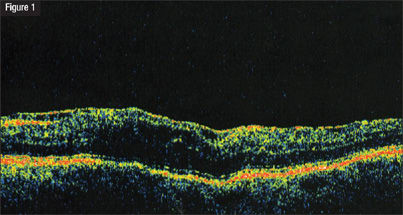

To confirm my suspicions, I used the Stratus OCT to examine the patient's retina in the left eye. Results showed that she had an ERM with foveal traction and an internal limiting membrane (ILM) (Figure 1).

| The Stratus OCT shows an epiretinal membrane (ERM) with foveal traction (left) and an internal limiting membrane (ILM) OS. A vitrectomy was performed to remove the ERM and ILM. The retinal surface smoothed out (right) several weeks after surgery. | |